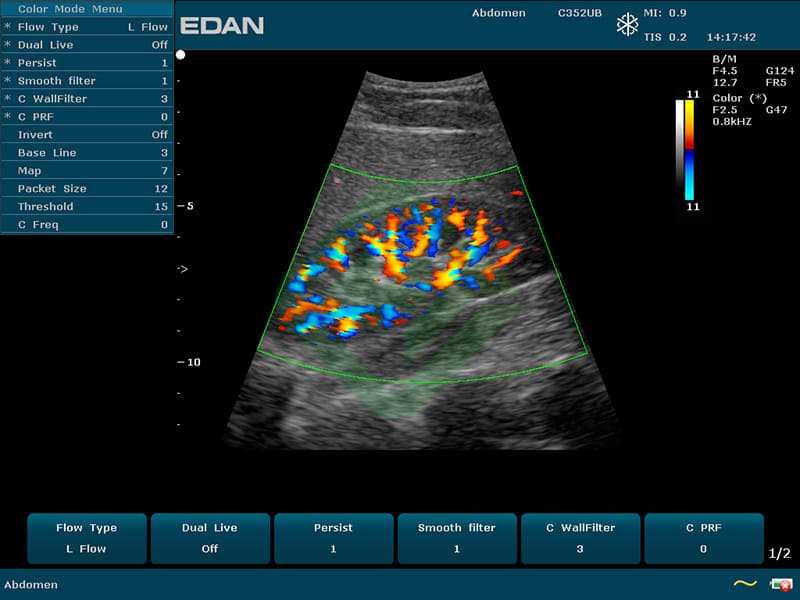

— цветовое доплеровское картирование

— направленная энергетическая доплерография

— конвексным C352UB: частотный диапазон датчика 2–6 МГц, угол обзора 70°, глубина сканирования 320 мм, количество элементов 128